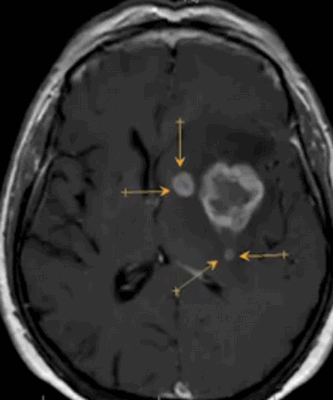

Метастазы в головном мозге на постконтрастном изображении (указаны стрелками)

Может ли МРТ показать опухоль головного мозга?

По результатам магнитно-резонансной томографии врачи могут выявить изменения структуры тканей. Опухоли головного мозга на МРТ определяют по прямым и косвенным признакам. Врачи подозревают патологическое образование по типу и равномерности изменений МР-сигнала:

- гипо- (более слабый, чем окружающие области) или гиперинтенсивный (отклик сильнее, чем от нормальных зон);

- гетероизмененный (смешиваются разные характеристики);

- изоинтенсивный (опухоль выглядит, как другие ткани, но отличается от нормальной архитектоники мозга).

Существуют и косвенные признаки. Последние дают основания подозревать новообразование головного мозга на фоне изоинтенсивного отклика тканей или подтверждают ее наличие при измененном МР-сигнале.

Множественные метастазы в вещество головного мозга на МРТ без контраста

До- и постконтрастное изображение злокачественной опухоли головного мозга

С помощью МРТ при раке мозга выявляют локализацию опухоли, степень ее инвазии в соседние структуры, особенности кровоснабжения, стадию заболевания и наличие метастазов. Для получения дополнительных сведений, сканирование проводят в различных последовательностях (Т1, Т2, FLAIR, диффузно-взвешенное и пр.), в нативном режиме и после контрастирования.

В заключении описывают зоны измененного МР-сигнала, их локализацию, размеры, контуры, наличие масс-эффекта, признаков перифокального отека и дислокационные явления. Выводы рентгенолога нельзя считать диагнозом. Результаты исследования должен изучить врач, который инициировал диагностику, или онколог. На поздних стадиях развития заболевания по структуре и характеристикам опухоли можно с большой долей вероятности определить ее тип. Окончательный диагноз ставят с учетом результатов других исследований.

- метастазы. Выглядят, как множественные образования в тканях головного мозга различных размеров, неправильной формы, с неровными контурами, накапливающие контраст, с различной интенсивностью отека вокруг;